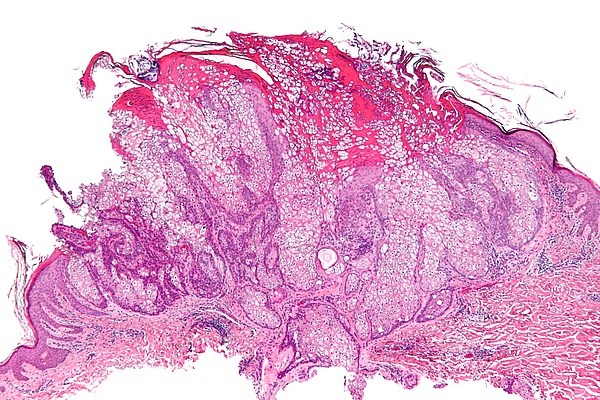

- Гистологические исследование аденомы сальных желёз[3].

При гистологическом исследовании выявляется, что опухоль располагается в дерме и состоит из множества долек различной величины и формы, часто очень крупных, особенно в центральных отделах. Дольки отграничены друг от друга тонкими прослойками соединительной ткани и состоят из клеток двух типов — ростковых и зрелых клеток сальной железы. Ростковые клетки имеют маленький размер с округлым или овальным ядром и скудной базофильной цитоплазмой без признаков жира. Зрелые клетки имеют крупный размер, полигональной формы, с чёткими границами, округлым светлым ядром и пенистой цитоплазмой, содержащей жир. Между этими клетками имеются переходные формы[1]. Признаки атипии или инвазивный рост отсутствуют[2].